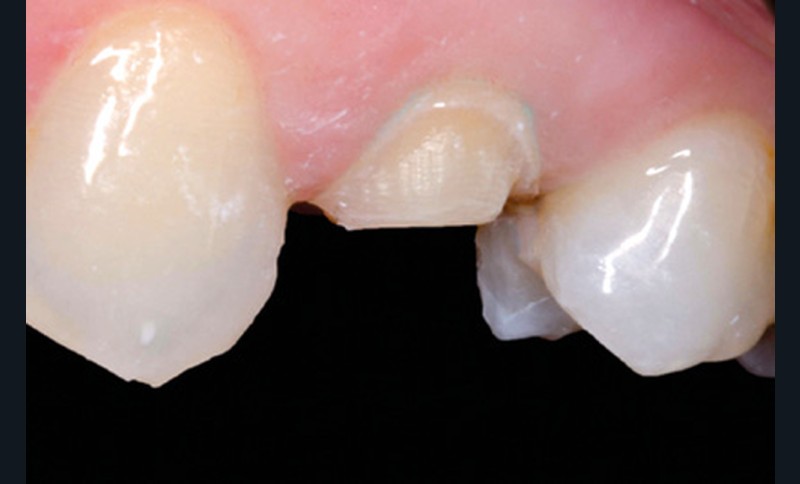

Mme B. se présente au cabinet pour une douleur au niveau de la 24. La dent présente une ancienne restauration avec une lésion carieuse, ainsi qu’une fêlure en mésial avec une pulpite irréversible. La décision est prise de dévitaliser la dent puis de la restaurer par un veneerlay (fig. 11).

Une empreinte optique de l’arcade, de l’antagoniste, ainsi qu’une empreinte de l’occlusion sont réalisées avant la préparation. Tous ces éléments vont aider le prothésiste dans le dessein de sa restauration. Le fichier est ensuite gommé au niveau de la dent préparée, puis enregistré (fig. 12 et 13).

La pièce prothétique est dessinée sur un logiciel de modélisation dentaire, puis elle est imprimée en résine calcinable et transformée en céramique (disilicate de lithium) par technique pressée (fig. 14).